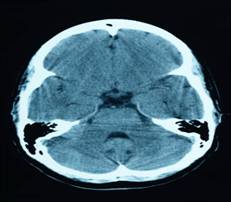

- CTE is a progressive degenerative disease, which can currently only be definitively diagnosed postmortem, in individuals with a history of multiple concussions and other forms of head injury.

-CTE occurs when repetitive head trauma begins to produce abnormal proteins in the brain known as “tau.” The tau proteins work to essentially form tangles around the brain’s blood vessels, interrupting normal functioning and eventually killing nerve cells themselves. Patients with less advanced forms of the disease can suffer from mood disorders, such as depression and bouts of rage, while those with more severe cases can experience confusion, memory loss and advanced dementia.